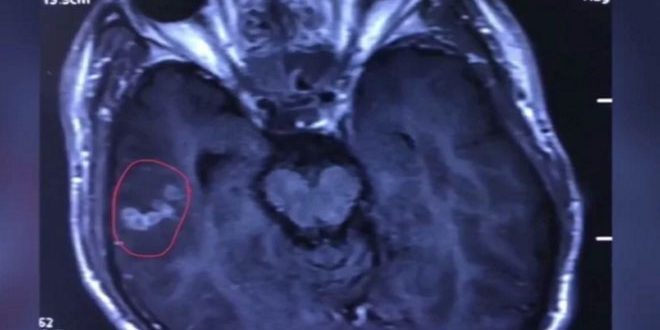

أخرج جراحون صينيون دودة شريطية بلغ طولها 10 سنتيمترات من دماغ رجل تعود على تناول اللحوم بدمائها.

وأضافت: نتيجة لذلك أرسل إلى المستشفى المركزي في المدينة حيث أجريت له اختبارات دم أظهرت نتائجها أن دودة شريطية تعيش داخل جسمه ولاحقاً تمكن الأطباء من تحديد مكانها وأجريت له عملية وتم إخراج الدودة من دماغه.